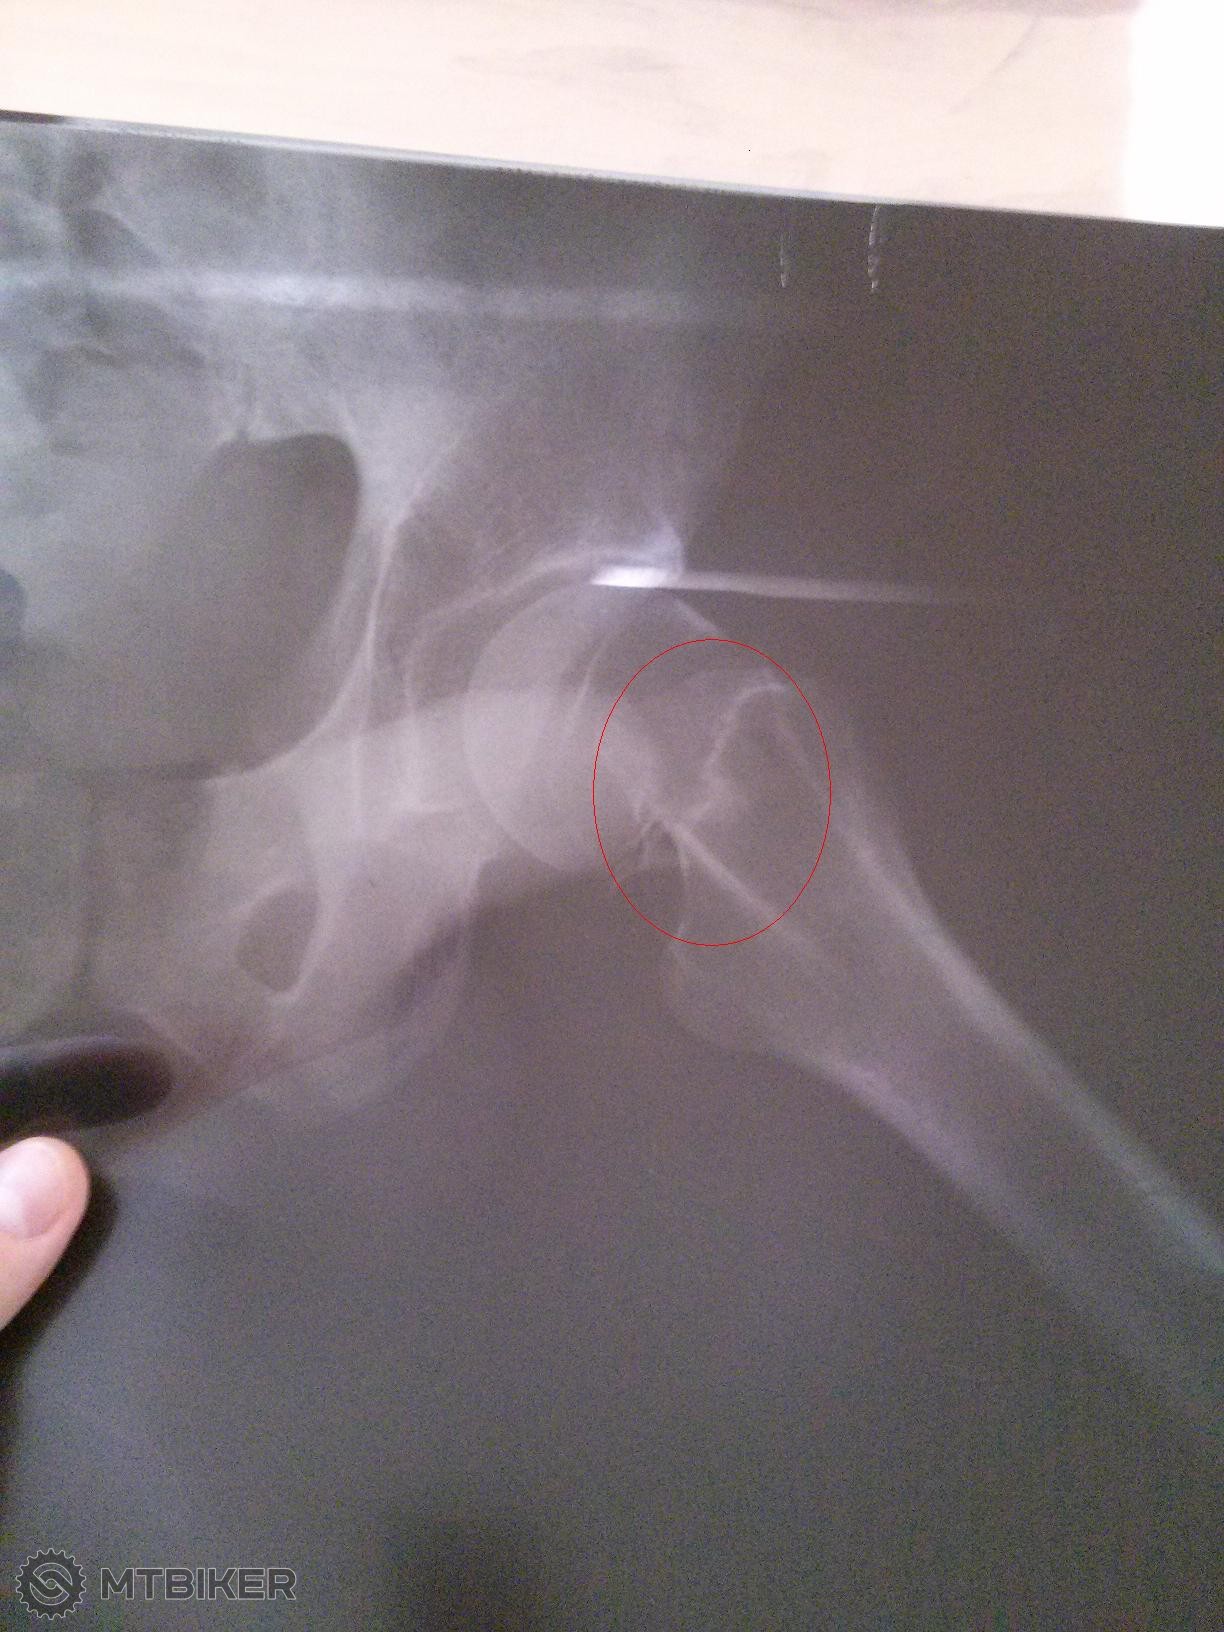

marina_militare kukal som RTG snimok co si sem postol. Nesrobovali ti to, len cisto fixacia nohy? Minimalne by som si zobral kontrolny RGT snimok po 6tyzdnoch a skonzultoval to s nejakym ortopedom. Pokial je tvoj lekar traumatolog, vidi celu tvoju nohu/uraz mozno kus inac ako ortoped - to iste plati o rehabilitacii. Na tvojom mieste by som na to isiel zlahka nakolko mas oslabene svaly a tym padom vaziva nachylne na uraz. 10dni teraz pravidelne cvicenie skor frekvencne urcite nie silove - rotoped rozne flexie clenku zamerane na mobilitu. Pri rehabkach plati ze bez ziskania celeho rozsahu pohybu nie je mozne spravne vykonavat silove cvicenia a teda korektnu regeneraciu svalstva. 10 dni cvic v 10min intervaloch kazdu polhodku a nechod za hranicu bolesti.

nakoniec som cakal na voziku na chodbe na urgente 2 hodiny, kym ma zobrali dnu, urobili RTG a uz to zacalo, diagnoza zlomenina krcka stehnovej kosti a uz lietali so mnou hore dole. prijali ma o 2 poobede a o 6 vecer som bol uz na operacke. mam 4 sruby, platnu, 8 tyzdnov prisne bez zataze nohy len o barlach, po 8 tyzdnoch kontrola a ak to bude ok, tak dalsi mesiac francuzske barle a postupna zataz nohy, plna zataz najskor o 3 mesiace.